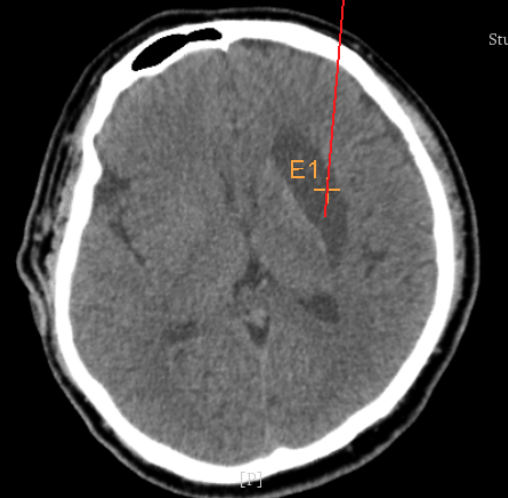

術前CT:血腫已經(jīng)液化,但仍有占位效應

alt text

增強核磁提示:血腫液化周邊增強